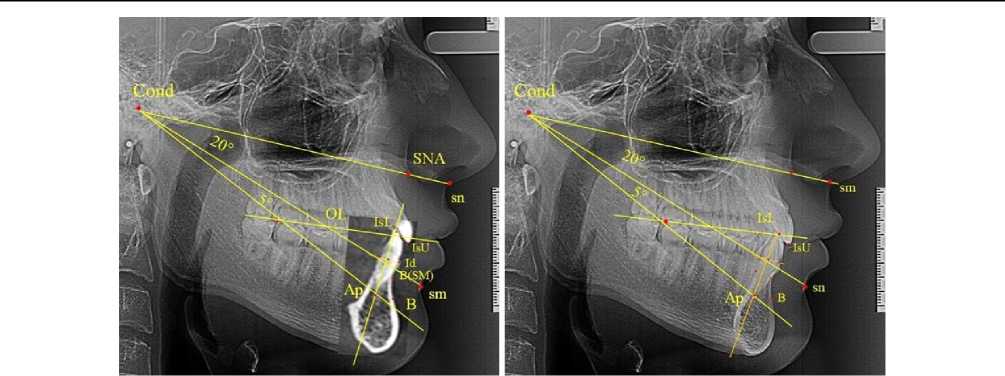

При анализе терентгенограмм (ТРГ) устанавливали общепринятые точечные ориентиры для анализа гнатической части черепа. На вершине суставной головки нижней челюсти устанавливали точку Cond. На передней носовой ости верхней челюсти определяли положение точки SNA. Режущий край нижнего резца обозначали точкой IsL, а верхнего резца – точкой IsU. Передняя выступающая точка альвеолярной части нижней челюсти вблизи шейки нижнего резца с вестибулярной стороны (инфрадентальная точка) обозначалась точкой Id. Точка наибольшей вогнутости альвеолярной части соответствовала положению апикальной точки Downs и обозначалась традиционно B(SM). На мягких тканях определяли положение субназальной точки sn на месте перехода носовой перегородки в верхнюю губу. Наибольшая вогнутость мягких тканей подбородка определяла положение супраментальной точки sm. Кроме того, проводили уловную срединную вертикаль нижнего резца через верхнюю точку резца и середину шей- ки проксимальной поверхности на уровне инфра-дентальной точки. Сложность определения проекции верхушки корня нижнего резца, определяющая положение апикального базиса нижней челюсти по Schwarz, на боковой телерентгенограмме обусловлена наложением рентгеноконтрастных соседних костных структур. В связи с этим использовали метод наложения фрагмента конуснолучевой компьютерной томограммы (КЛКТ) на телерентгенограмму в программе PowerPoint (рис. 1).

а                                                б

Рис. 1. Расположение диагностических точек на ТРГ (а) и в сочетании ТРГ с наложенным резцовым сегментом КЛКТ

На совмещенном снимке определи положение верхушки корня нижнего медиального резца, которую обозначали литерами Ap . Измеряли расстояние от режущего края резца до апикальной точки, которое использовали для определения апикальной точки B по Schwarz на передней стенки костной ткани альвеолярной части нижней челюсти. При этом расстояние IsL-Ap было равно расстоянию IsL-B .

От суставной точки Cond проводили радиальные линии до кожных ориентиров sn и sm с последующим анализом угла гнатической части лицевого отдела sn-Cond-sm , который определял высоту прикуса и служил в качестве диагностического критерия аномалий окклюзии в вертикальном направлении. Линия Cond-Ар проходила через апикальную точку нижнего резца на совмещенной томограмме с телерентгенограммой и позволяла в последующем на латеральной телерентгенограмме определять положение апикальной точки.

Учитывая сложность определения апикальной точки нижнего латерального резца на ТРГ, ее местоположение определяли после совмещения ТРГ с фрагментом резцово-челюстного сегмента КЛКТ. На этом основан предложенный метод определения апикальной точки нижней челюсти по Schwarz. Во-первых, проводилось построение угла sn-Cond-sm и от точки Cond к линии Cond-sm проводилась линия, пересекающая условную срединную вертикаль резца нижней челюсти. Место пересечения соответствовало положению апикальной точки нижнего медиального резца. Проекцию точки апикального базиса (точка В по Schwarz) отмечали, используя равенство расстояний IsL-Ap = IsL-B (рис. 2).

Рис. 2. Результаты анализа углов ТРГ с сегментом КЛКТ (а) и ТРГ (б) при определении положения нижней апикальной точки (В) по Schwarz

Результаты измерения угла sm-Cond-В' показали, что в группе людей с физиологической окклюзией угол составлял (5,03 ± 0,49)°, что позволило использовать полученные данные при анализе положения апикальной точки медиального нижнего резца на ТРГ в боковой проекции.